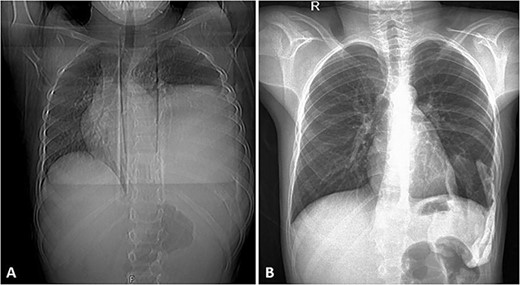

His postoperative course was uneventful. A chest CT was performed following the surgery, and the results revealed that the previous left lung mass had been completely removed without definite residue (Fig. 4). The patient is on close follow-up monthly with a physical exam, chest X-ray, and chest CT every 3–6 months. For the past two years, there have been no discernible clinical or radiological indicators of recurrence (Fig. 5).

(A) Frontal chest radiograph of the same patient showing a left-sided opacity involving the left middle and lower lung zones and silhouetting the diaphragm and the left cardiac border in keeping with the known huge left posterior chest wall tumor. Widening of the posterior aspect of the left 10th intercostal space is noted. (B) Frontal chest radiograph taken during follow-up visits ~2 years following the surgical resection of the tumor, it shows re-expansion of the left lung with no residual or recurrent masses.